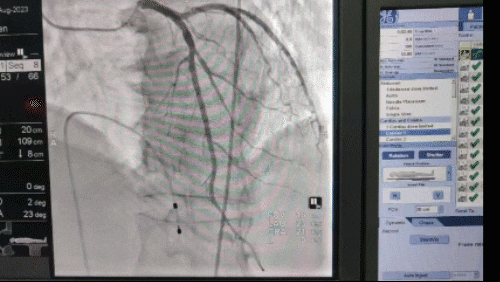

进入导管室。

16:38

临时起搏器装入成功。

16:49

心脏血管造影提示左右冠脉均通畅,考虑血管痉挛解除、血栓自溶,术后患者神志清醒,生命体征平稳,转入 CCU 进一步观察治疗。漳州市第三医院胸痛团队,通过早期的生命救治链,为危重症患者抢救争取了宝贵的时间。